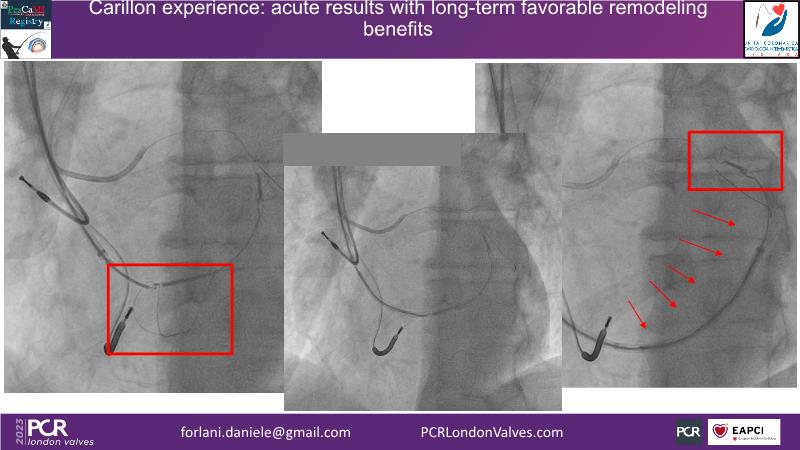

This session offers insights into combo therapy involving Carillon for patients with functional mitral regurgitation. It covers details of the EMPOWER trial, a double-blinded, sham-controlled study, and explores the potential benefits of early treatment for patients with functional mitral regurgitation.